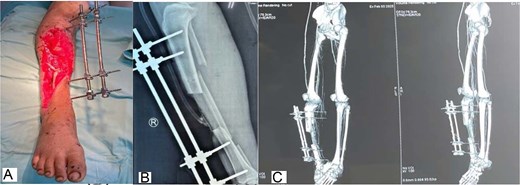

After serial radical debridement, an extensive anteromedial soft-tissue defect (approximately 14 × 25 cm) with exposed tibia and a 7-cm segmental tibial defect remained (Figs 1 and 2). Computed tomography angiography demonstrated occlusion of the anterior tibial artery and distal peroneal artery, leaving the posterior tibial artery as the only functional runoff.

Initial injury and preoperative imaging. (A) Initial presentation of a Gustilo–Anderson type IIIB open fracture of the right tibia. (B) Preoperative anteroposterior radiograph demonstrating a comminuted open tibial fracture with segmental bone loss.

The wound was optimized using repeated debridement and circumferential negative-pressure wound therapy that enclosed the limb and external fixation (Fig. 2C), promoting granulation tissue (Fig. 3A). Definitive reconstruction (6 February 2025) used a vascularized pedicled fibular graft from the injured leg, fashioned to bridge the tibial defect and secured with screws and wires, while the external fixator maintained alignment (Fig. 3B and C).

Wound-bed preparation and bony reconstruction imaging. (A) Granulation tissue formation after serial debridement and continuous negative-pressure wound therapy. (B) Postoperative radiograph showing the vascularized pedicled fibular graft bridging the tibial defect; the external fixator maintained limb stability during recovery. (C) Postoperative three-dimensional computed tomography reconstruction confirming graft position spanning the tibial defect with stabilization by external fixation.